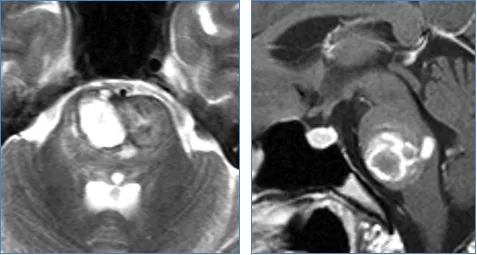

18岁患者米拉突发剧烈头痛后,出现左侧肢体功能障碍、面部歪斜及饮水呛咳等症状,短期内发展为卧床状态。经检查确诊为桥脑部位海绵状血管瘤破裂,该区域传统被视为手术禁区。

患者临床表现包括急性头痛、左侧轻偏瘫(2级)、面瘫、严重吞咽困难及卧床不起。巴教授凭借30余年脑干手术经验,成功实施病灶切除手术。术后患者面瘫症状改善,神经功能恢复良好。

巴教授根据桥脑解剖结构与病变复杂关系,总结五大手术入路:经髓帆入路、经桥脑臂入路、远外侧入路、小脑上外侧入路、颞颞下经天幕入路。具体入路选择需结合患者个体情况及主刀医生经验综合决定。远外侧入路示意图显示延髓脑桥沟区域为脑干安全进入区。桥脑海绵状血管瘤病变位置虽不直接邻接桥脑表面,但会单侧移动周围结构,包括外展神经和面神经等重要组织。